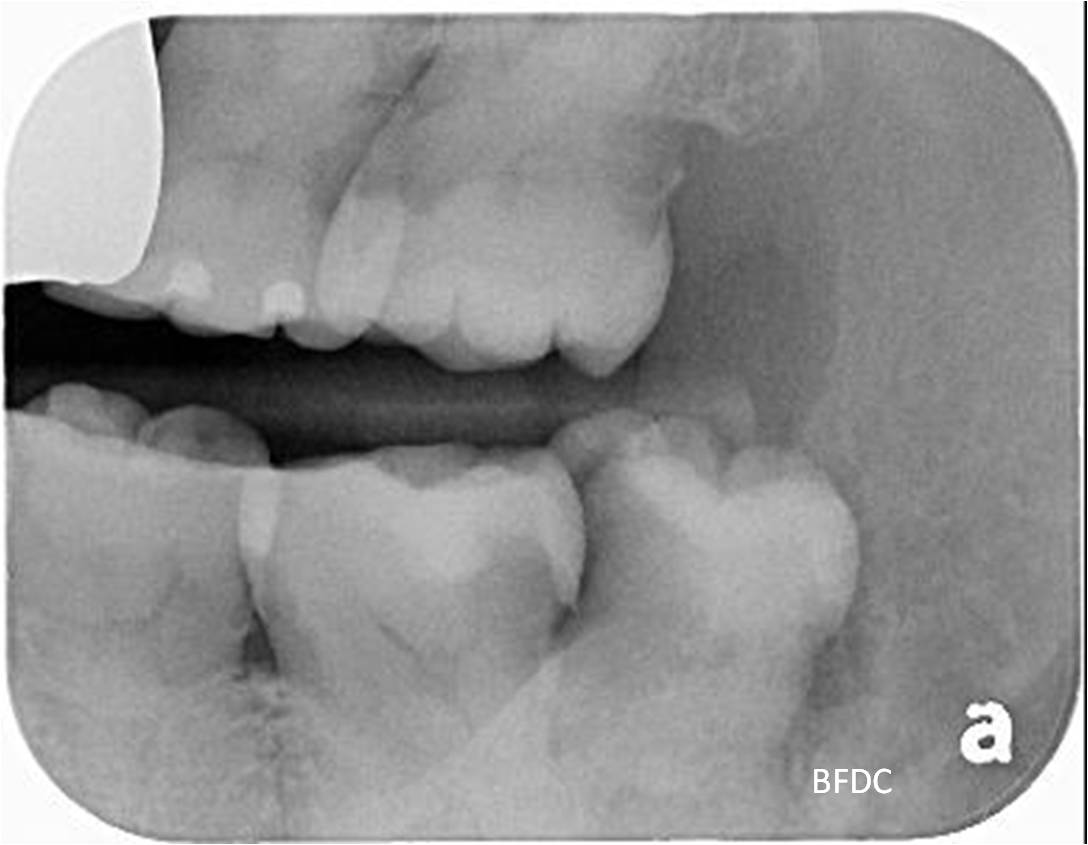

治療前,因智齒蛀牙,容易卡食物

蛀牙已至牙髓,建議先拔除智齒